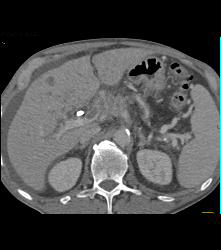

Gastrinoma